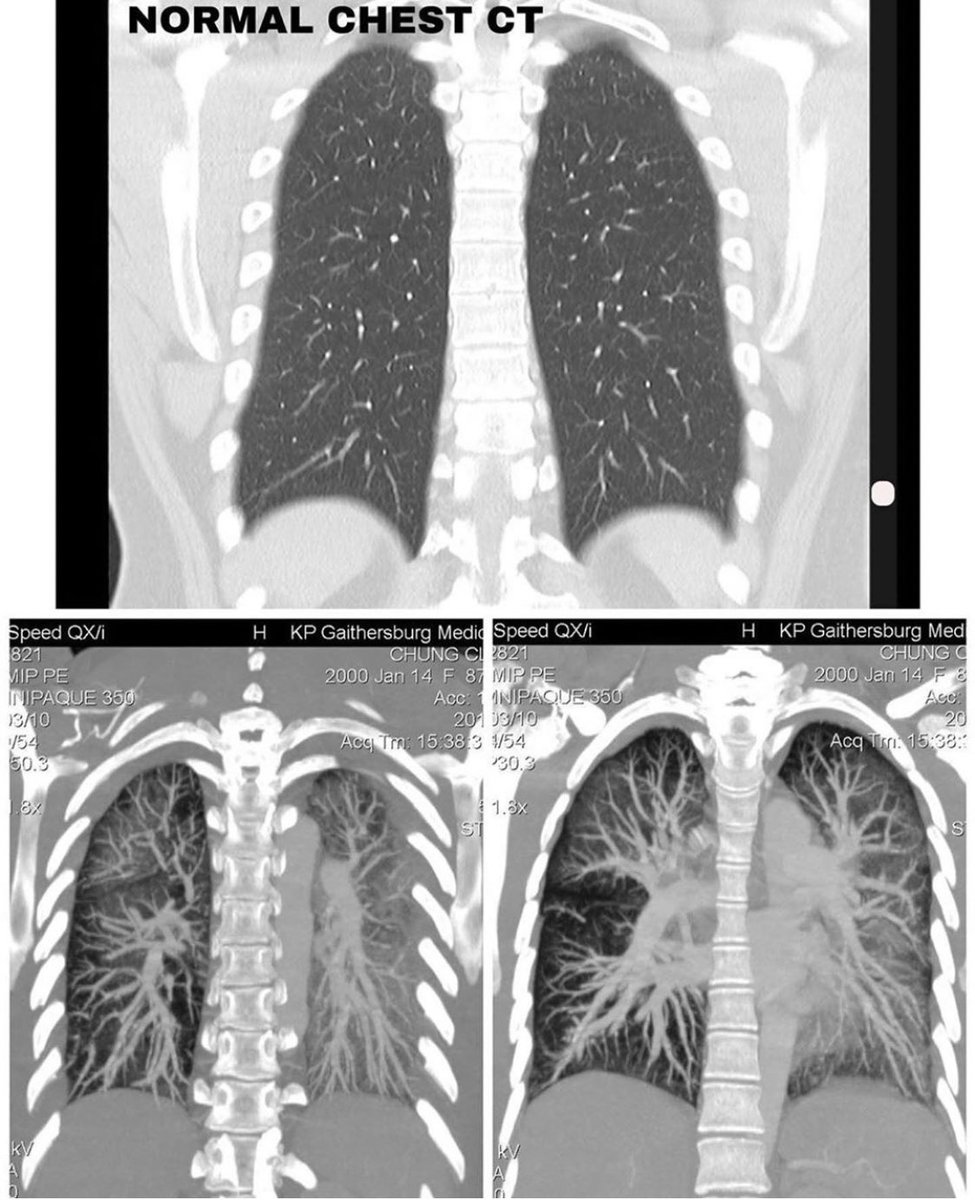

بينت الأشعة المقطعية تزايد في منطقة "الالتهاب" لتشمل الرئتين بالكامل، ولذلك تم تنويمها في العناية المركزة تحت العزل التنفسي والبدء في مضادات حيوية عن طريق الوريد